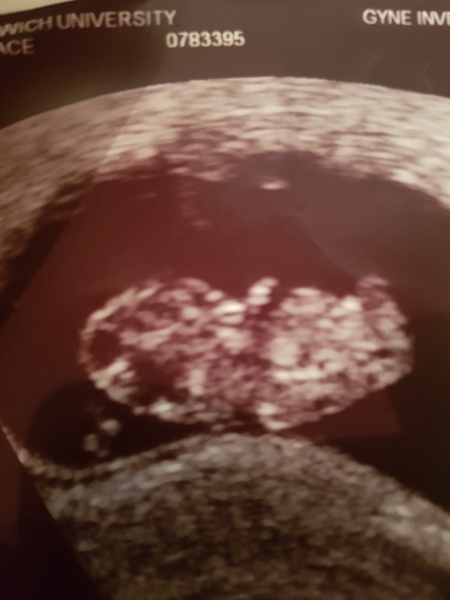

@Babymummasoontobe4 im so glad your scan want well! Them little feet. Too cute! I've got my scan tomorrow. Should be 9+3, hopeful for good news. My anxiety is through the roof! Did you get to see the little one moving?

@SavanahXx hey thank you my anxiety went through the roof whilst I was being scanned I was shaking so much much I could hardly breath..omg it was amazing the little legs were moving about and the heart was beating so fast,they let me sit and look at the screen for a few minutes which was lovely..good luck for today,you will be fine,enjoy seeing youre baby 😘

@Babymummasoontobe4 thank you for your kind words. I panicked and prepared myself for the worst for no reason! Baby's absolutely fine and even waved at mummy and daddy. They pushed my date back by 2 days, so I'm now 9+1. I'm so glad the little bean is ok 😆😆

@Babymummasoontobe4 it was amazing. I sat there and said "why does the baby chose to be asleep at the times i want to see him or her moving?" And the baby started to wiggle and then waved at us 😆😆😆 an amazing moment. Now I just have to get to the 12 week milestone. Got my fingers and toes crossed. And ive just done a new calculation online and going off my scan date and how many weeks i am, I'm due on the 8th September too!! X